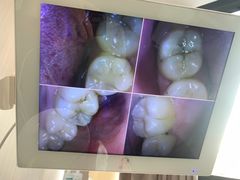

• 同步齿科·数字化正畸种植口腔中心(珠海店)

• -同步齿科·数字化正畸种植口腔中心(珠海店)

木木倩 | 24-01-31